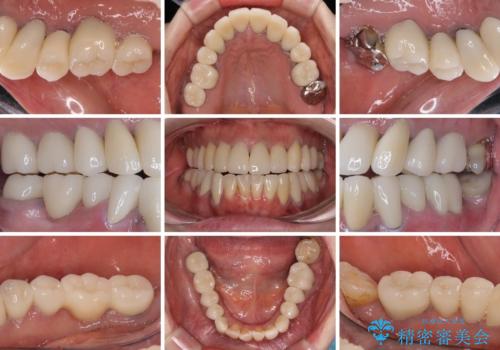

仮歯で咬み合わせの調整を行ってからは、特に不安定になることもなく、非常にスムーズに治療を進めて行くことができました。

前歯奥歯ともに望ましくない力がかかりやすい咬み合わせであるため、就寝時にはマウスピースを使用するようにお伝えしております。